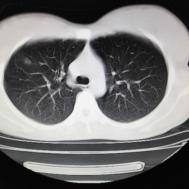

支原体肺炎1例CT影像表现

性别:女,年龄:26岁,低热,轻微胸痛,支原体阳性

[影像描述]

两肺内及胸膜下多发斑片状高密度影,部分病灶密度较淡,部分实变,边缘可见渗出改变。